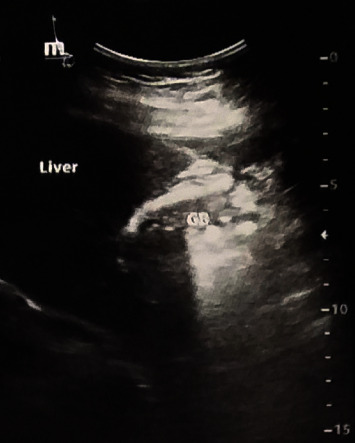

Background: Gallbladder agenesis (GA) is a very uncommon disorder of the biliary system. Diagnosis of GA can be difficult and may result in unnecessary procedures. In this case report, we will discuss our experience with an intraoperative accidental diagnosis of GA in a middle-aged woman that was effectively treated. Case Presentation. A 46-year-old woman presented with abdominal pain, nausea, vomiting, and intolerance to meals. Laparoscopic surgery was conducted based on sonographic imaging and a preliminary diagnosis of chronic cholecystitis. No gallbladder was seen during laparoscopy, and the patient was diagnosed as a case of GA. The laparoscopy was terminated, and the patient was referred for magnetic resonance cholangiopancreatography (MRCP) to confirm the diagnosis. Finally, endoscopic retrograde cholangiopancreatography (ERCP) and sphincterotomy were performed to alleviate symptoms. After one year of follow-up, the patient's overall condition is satisfactory and symptom-free.